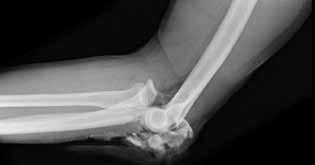

Question 8

Question 11

A 5-year-old boy falls from monkey bars and sustains a Gartland type III supracondylar humerus fracture. On presentation to the emergency department, his hand is pale and pulseless, but he has brisk capillary refill and normal motor function of the hand. What is the most appropriate next step in management?

Explanation

Correct Answer: Closed reduction and percutaneous pinning, followed by reassessment of the pulse

In a pulseless but well-perfused (pink, brisk capillary refill) hand following a displaced supracondylar humerus fracture, the initial step is urgent closed reduction and percutaneous pinning. Often, the brachial artery is kinked, tethered over the proximal fracture fragment, or in spasm, and anatomic reduction restores the pulse. If the hand remains pulseless and becomes poorly perfused (white/ischemic) after reduction, open exploration of the brachial artery is indicated. CT angiography delays definitive treatment and is not indicated in the acute setting of a pulseless, pink hand.

A 5-year-old boy is brought to the emergency department after falling from monkey bars. He sustained a completely displaced extension-type supracondylar humerus fracture. His hand is pink and well-perfused, but he is unable to make an "OK" sign with his thumb and index finger. Which of the following structures is most likely injured, and what is its typical anatomical course at the elbow?

Correct Answer: A

The inability to make an "OK" sign indicates an injury to the anterior interosseous nerve (AIN), which innervates the flexor pollicis longus and the flexor digitorum profundus to the index finger. AIN neuropraxia is the most common nerve injury associated with extension-type supracondylar humerus fractures. The AIN is a motor branch of the median nerve, which passes between the humeral and ulnar heads of the pronator teres muscle in the proximal forearm.